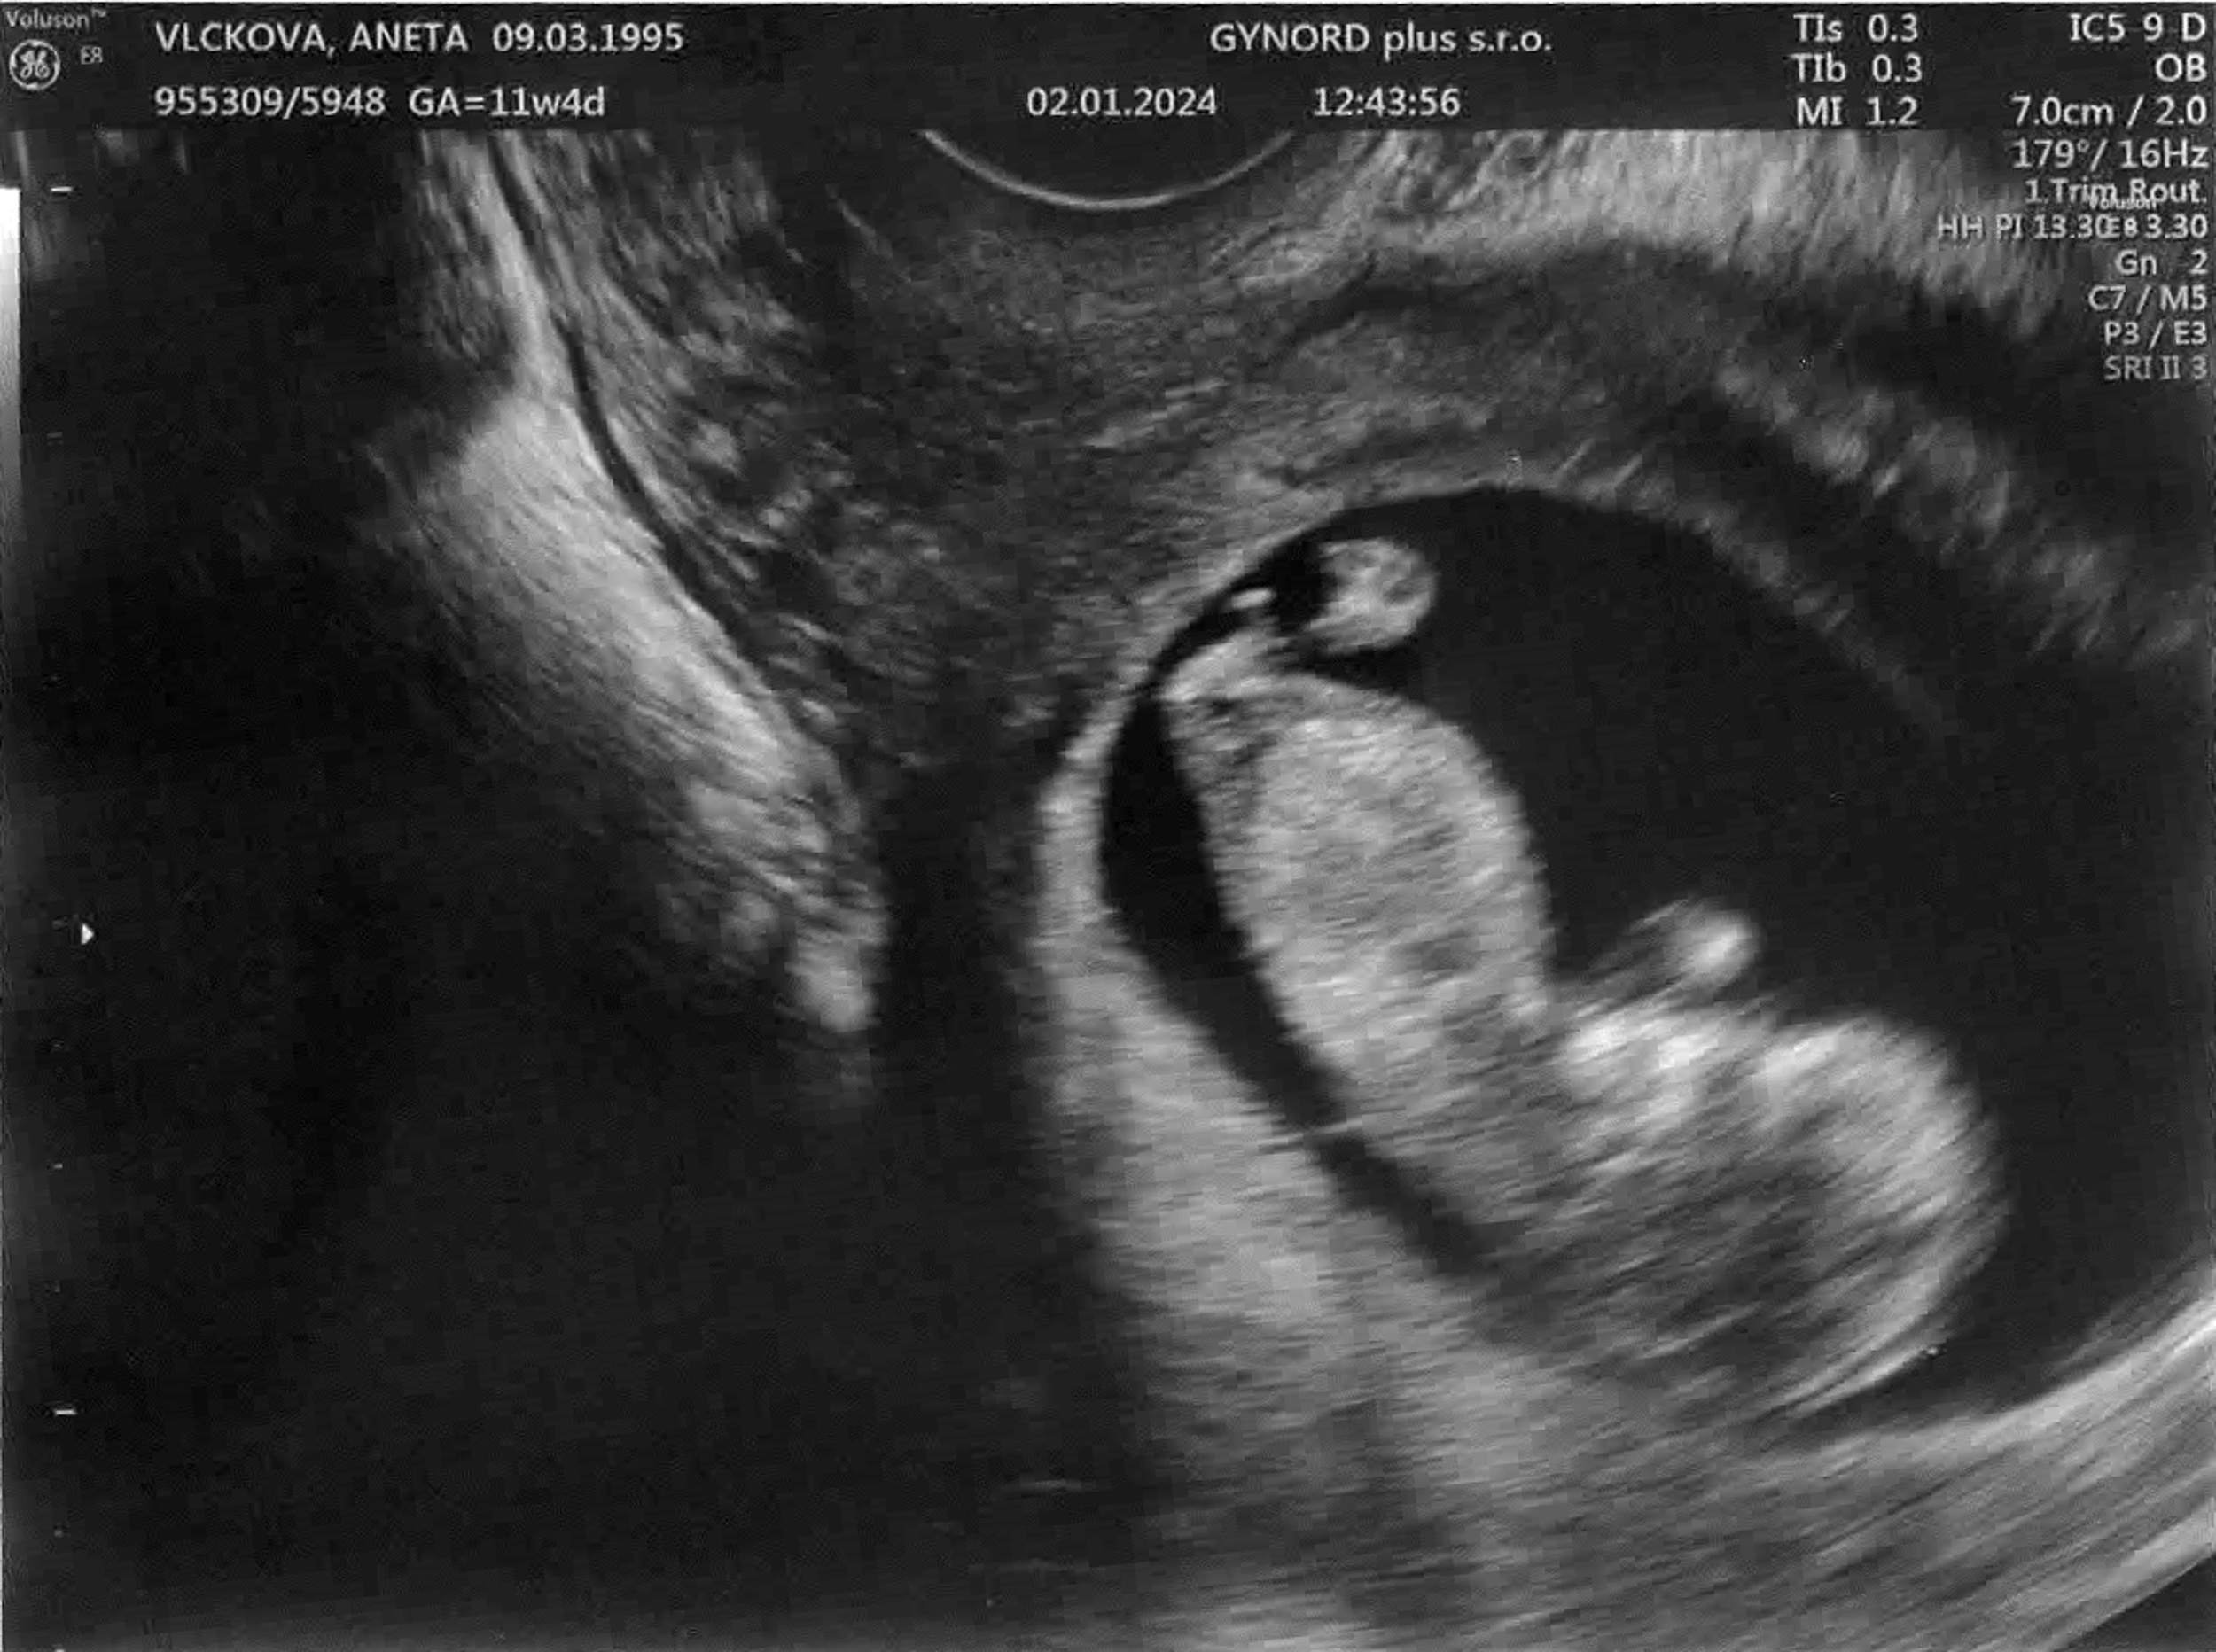

Tomášek - ještě v bříšku